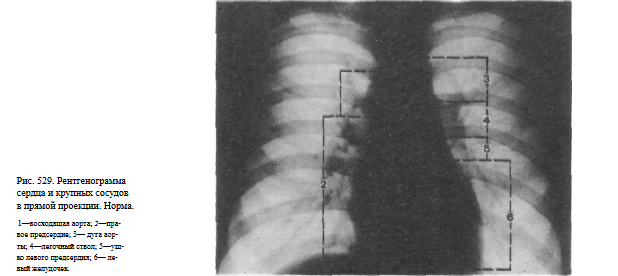

Рентгенограмма аорты

Рентгенограмма аорты 114 фотографий